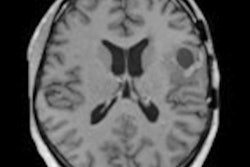

Using 7-tesla MRI to image the brains of glioma patients, German researchers have correlated the protein content of those tumors with patient response to treatment and likelihood of survival, according to a study published online on 26 February in European Radiology.

A conventional morphological contrast-enhanced 3-tesla MR image of a brain tumor (left) versus protein measurement using 7-tesla MRI (right). Images courtesy of Dr. Daniel Paech and European Radiology."Malignant gliomas respond very diversely to treatment," explained lead author Dr. Daniel Paech, from the division of radiology at the German Cancer Research Center (DKFZ), in a statement. "In some of the cases, postoperative radiotherapy and chemotherapy are more effective than in others. And whether the tumor has, in fact, responded to treatment cannot be told before the first follow-up care exam six weeks after treatment ends."

For this study, Paech and colleagues utilized noncontrast-enhanced 7-tesla MRI to target the chemical exchange saturation transfer (CEST) effect between the proteins and free water in tissue. Because cancer cells grow in an uncontrolled manner, they produce proteins in an equally uncontrolled manner, Paech noted.

"Our study shows that the protein signal measured in the [7-tesla] MR image is a biomarker that is associated with survival as well as with treatment response of patients: The stronger the protein signal, the poorer the prognosis," he said.